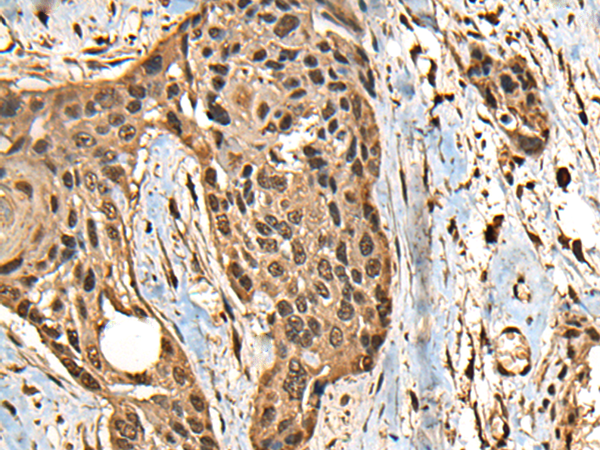

分类: 科研抗体货号: P09467别名: SORORIN应用: IHC反应种属: Human

分类: 科研抗体货号: P09455别名: ST6N; SIAT1; ST6GalI应用: IHC反应种属: Human, Mouse, Rat

分类: 科研抗体货号: P09464别名: CEP2; BORG1应用: IHC反应种属: Human, Mouse, Rat